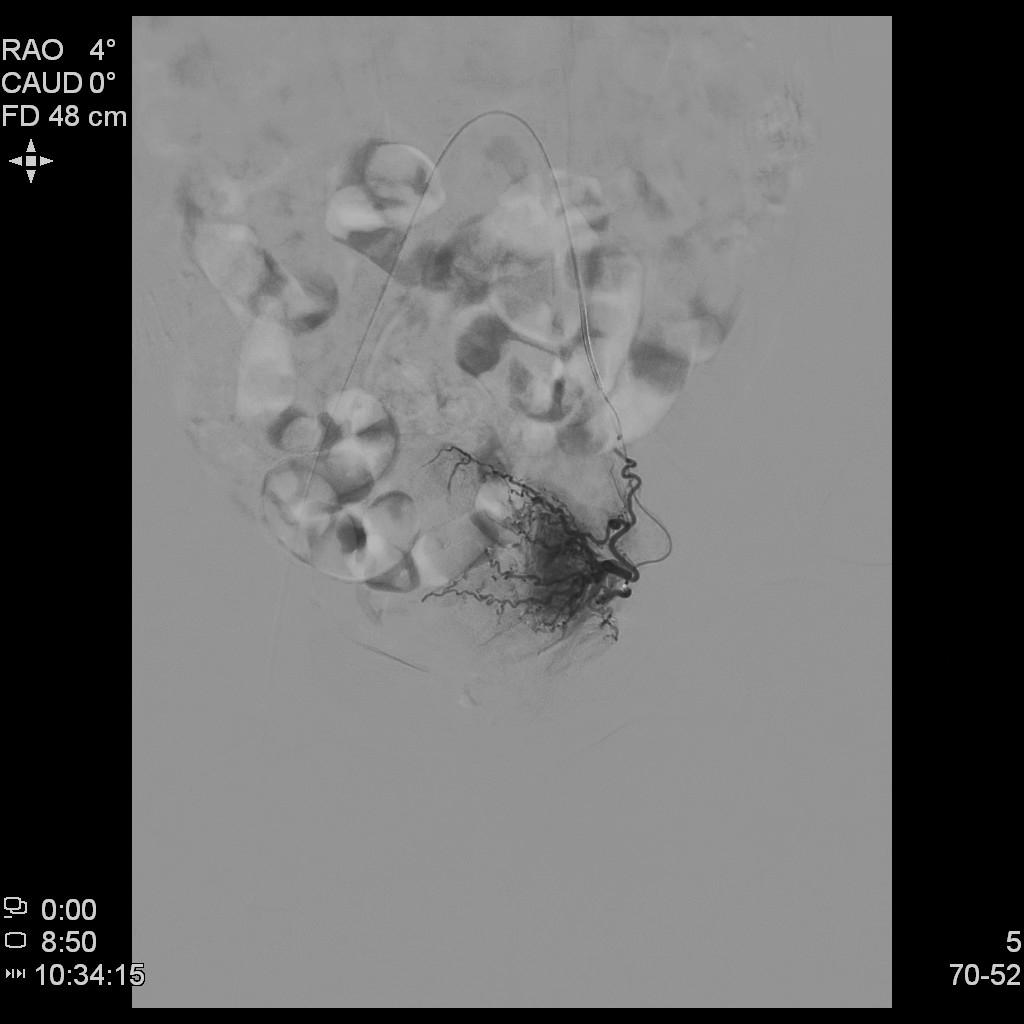

例3

中年患者,发现“子宫腺肌症”10年余,近5年痛经、月经量增多等症状明显加重,导致贫血,严重影响生活质量。

- 术前彩超、磁共振检查显示子宫明显增大,子宫前壁可见弥漫型子宫腺肌症病灶,合并粘膜下、肌壁间子宫肌瘤。

横断位

冠状位

矢状位

腹主动脉造影

左侧子宫造影

右侧子宫动脉造影

- 术后患者痛经、月经量过多症状迅速缓解,生活质量明显改善。